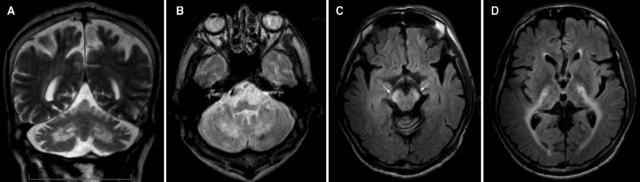

案例 5:1 例晚发 病患者。

图 5 A~B:T2WI 可见双侧半卵圆中心至内囊后肢的皮质脊髓束对称性高信号,胼胝体压部亦有受累

案例 6:44 岁女性,诊断为 病。

图 6 FLAIR / T2WI 提示脑白质病变,累及锥体束

案例 7:47 岁女性,诊断为亚历山大病。

图 8 A~C:FLAIR 可见延髓萎缩伴皮质脊髓束投射区高信号,双侧深部小脑白质和大脑半球高信号;D:T1 增强可见延髓和上颈髓萎缩

案例 8:60 岁男性,诊断为亚历山大病。

图 9 T2WI 可见明显的延髓萎缩 [a] 伴轻度小脑萎缩 [a~b],但脑桥基底部基本正常 [b],四脑室稍扩大 [b],中脑,特别是背侧,可见萎缩 [c];l:矢状位 T1WI 可见典型的蝌蚪状脑干萎缩,包括明显的颈髓-延髓萎缩,脑桥基底部完整,需注意,中脑被盖萎缩同样促成了「蝌蚪」的形成